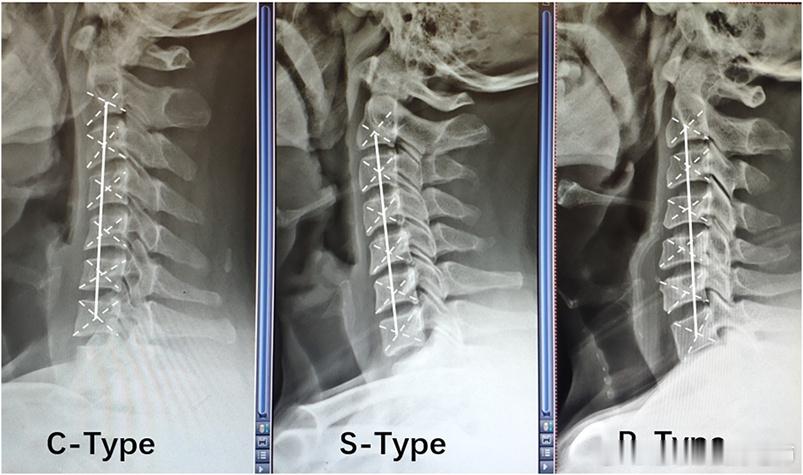

颈椎反弓 昨天讲了颈椎曲度变直,其实对于颈椎生理曲度变直或者反弓,也有不同的类型:

⚠️C型:所有颈椎椎体重心位于AB线后方

⚠️S型:椎体重心分布于AB线两侧,最靠后的椎体位于C5(第五椎体)以下

⚠️R型:椎体重心分布于AB线两侧,最靠后的椎体位于C5(第五椎体)以上